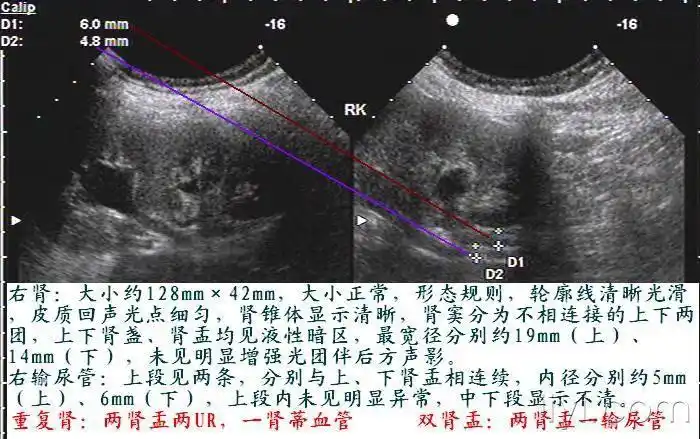

右侧重复肾1例图片集 - 超声医学讨论版 - 爱爱医医学论坛